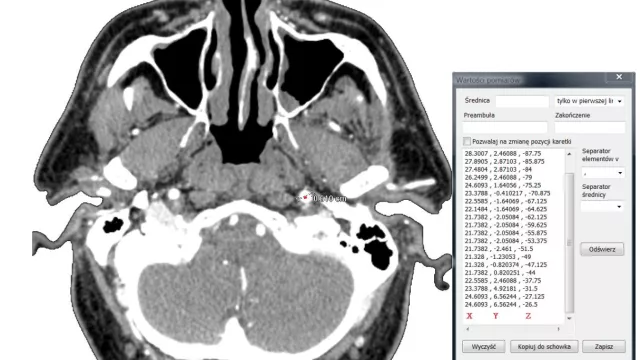

Jedną z przyczyn migrenowego bólu głowy, zawrotów czy omdleń mogą być problemy z niedokrwieniem mózgu. Do diagnostyki lekarze wykorzystują ultrasonografię dopplerowską lub tomografię komputerową. Zalety obu metod łączy zastosowanie narzędzi do modelowania przestrzennego oraz numerycznej mechaniki płynów opracowane w Instytucie Maszyn Przepływowych.